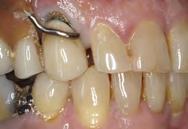

Figura 4. Aspecto de los pilares después de la aplicación de la radiofrecuencia. Arco dentario superior e inferior.

Después del desplazamiento gingival, se retiraron los tornillos de cicatrización de los implantes y se colocaron las cofias de impresión y cilindros posicionadores para tomar la impresión de los implantes a cucharilla cerrada; para la rehabilitación de implantes con sistema SynOcta,

se usó pilar atornillado Straumann (Figura 4).